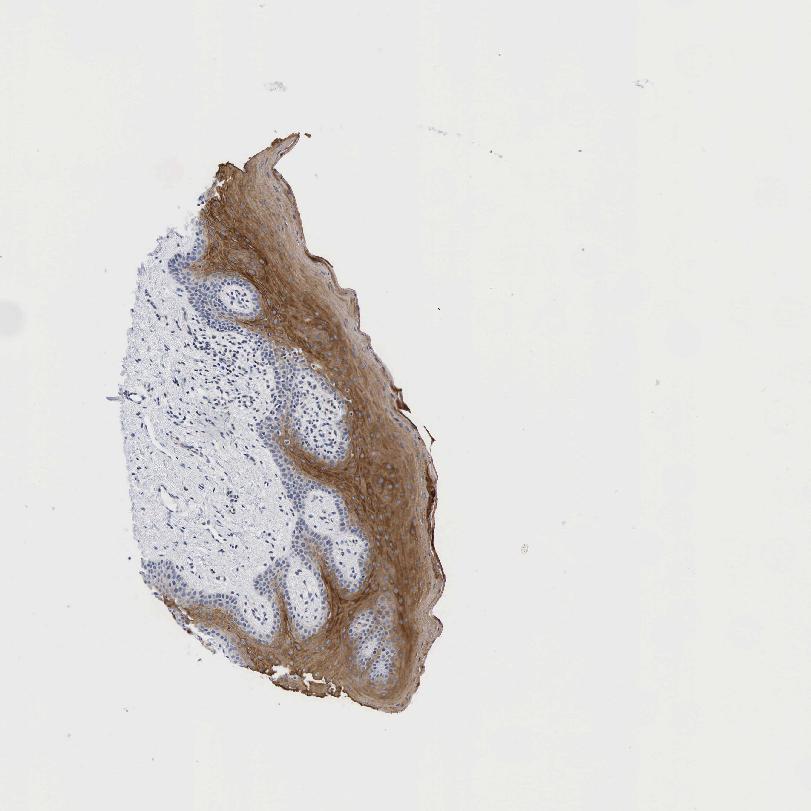

TISSUE PRIMARY DATA ORAL MUCOSA Show tissue menu

Oral mucosa

ORAL MUCOSA - Antibody stainingi

Antibody staining in the annotated cell types in the current human tissue is reported as not detected, low, medium, or high, based on conventional immunohistochemistry profiling in selected tissues. This score is based on the combination of the staining intensity and fraction of stained cells.

Each image is clickable and will lead to virtual microscopy that enables deeper exploration of all samples and also displays staining intensity scores, fraction scores and subcellular localization as well as patient and tissue information for each sample.

Antibody HPA004751Antibody HPA008428Antibody HPA017176Antibody CAB000068Antibody CAB055100

Squamous epithelial cells Not detectedNot detectedNot detectedHighNot detected